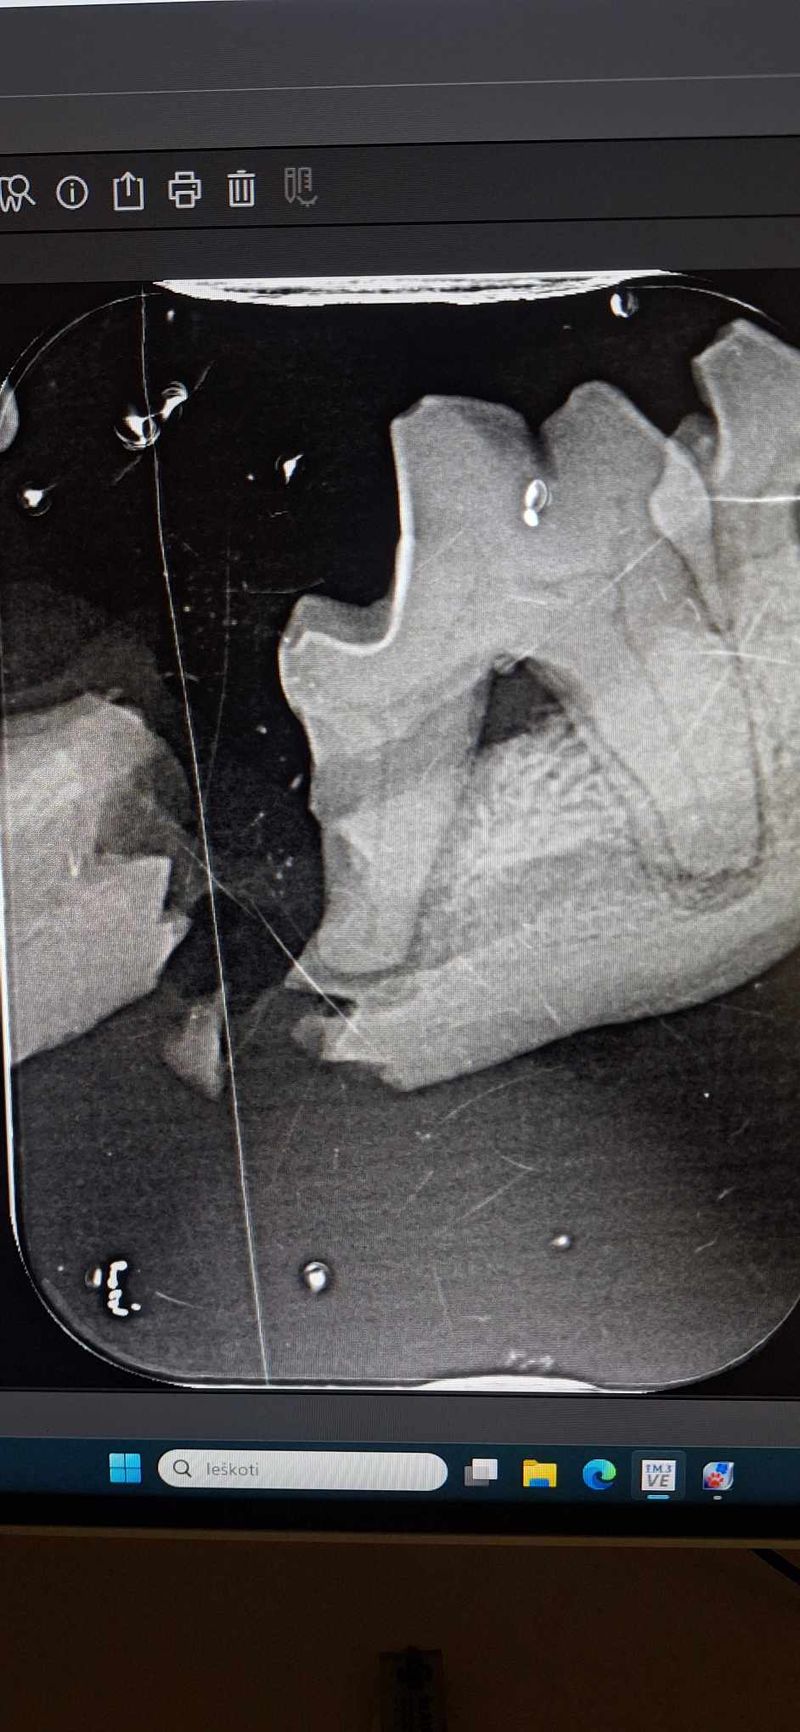

Policijos pareigūnų kovo 16 d. atvežtas sužalotas šuniukas į Šiaulių veterinarijos centrą, kovo 17 d. jau išoperuotas. Atsirado ir šeimininkai (Maksiuko..).